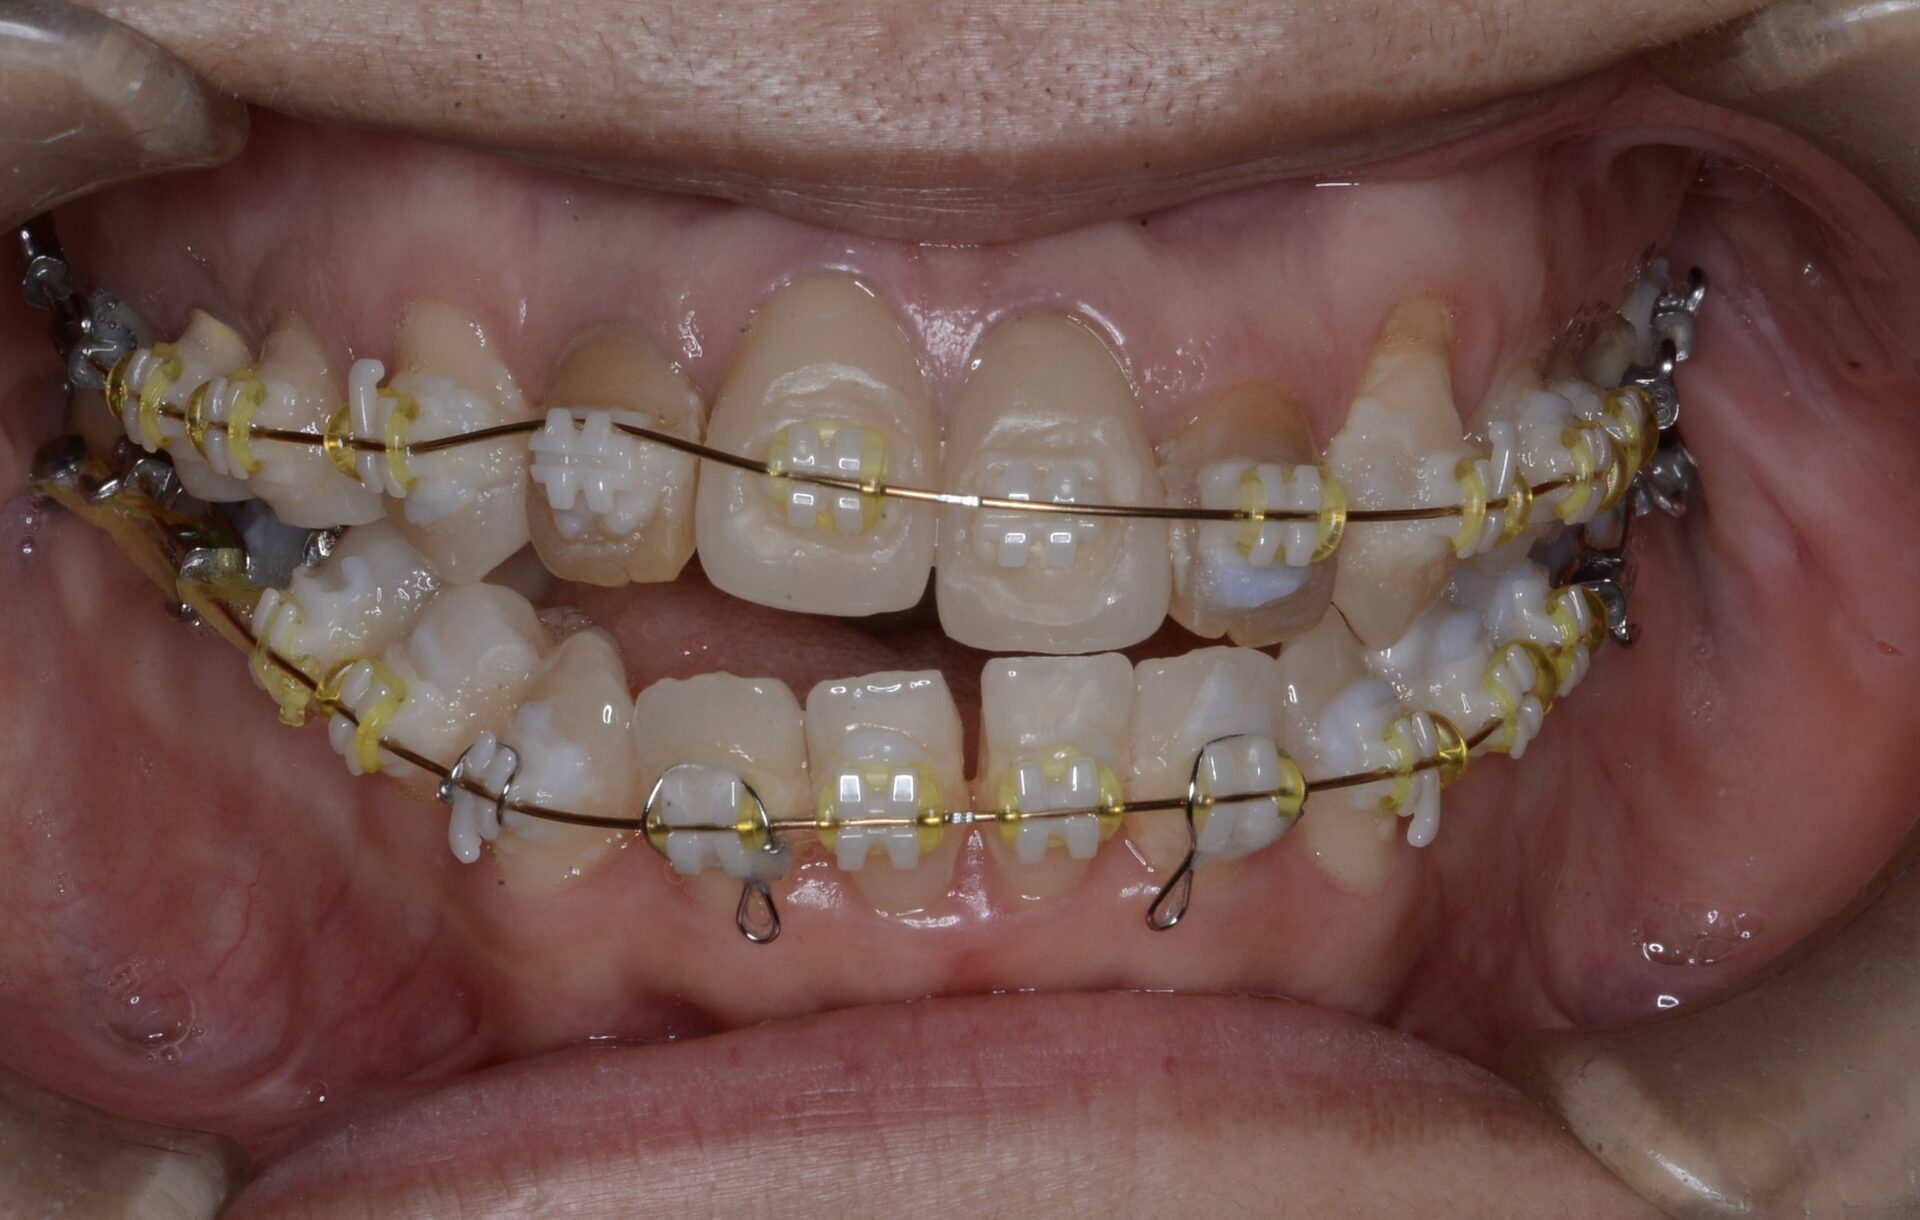

矯正中

アンキローシスを起こしている側切歯を理想的な形の仮歯に置き換え、それを周りの歯を動かしより下顎と咬合させるためのアンカーとして利用した。

オープンバイト(開口)になってしまった原因として下顎の親知らずが考えられるため、親知らずを抜歯してそのスペースに対して下顎大臼歯を圧下させたいが、親知らずが下歯槽管神経に近接しているため、すぐに抜歯することができず、親知らずの歯冠を削って少しずつ上に上がってくるのを待つ。